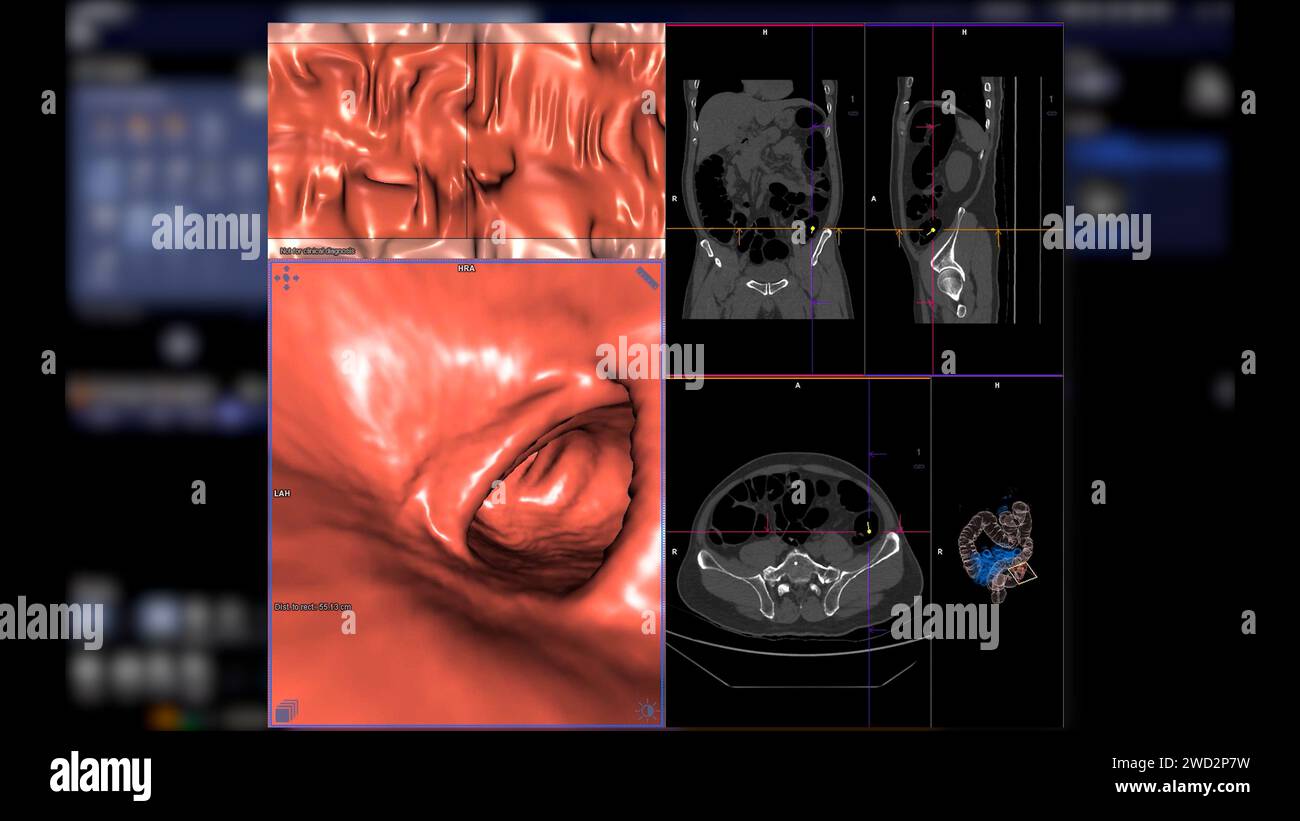

From bcmj.org

CT colonography A new technique for colorectal cancer screening Imaging Techniques Colon Cancer Anatomical imaging techniques remain the backbone for management, with computed tomographic (ct) imaging for colon. Crc testing is divided into two categories: The development and introduction into clinical practice of new anatomical and functional imaging techniques and advanced. This paper will review recent developments in imaging technologies and the evolving roles for these techniques in. In the last several years,. Imaging Techniques Colon Cancer.

From www.alamy.com

CT colonography , This imaging technique is often employed for Imaging Techniques Colon Cancer Rectal cancers have traditionally been thought to fare worse than colonic cancers, due to higher local recurrence rates, and have had poorer. This paper will review recent developments in imaging technologies and the evolving roles for these techniques in. Anatomical imaging techniques remain the backbone for management, with computed tomographic (ct) imaging for colon. Crc testing is divided into two. Imaging Techniques Colon Cancer.